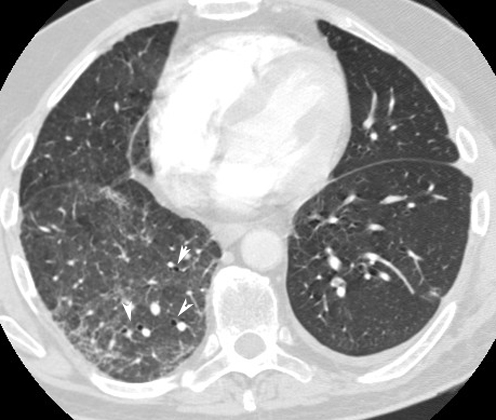

• Arrowheads point to bronchiectasis of lower lobe on right.

• Note artery next to dilated bronchi (signet ring).